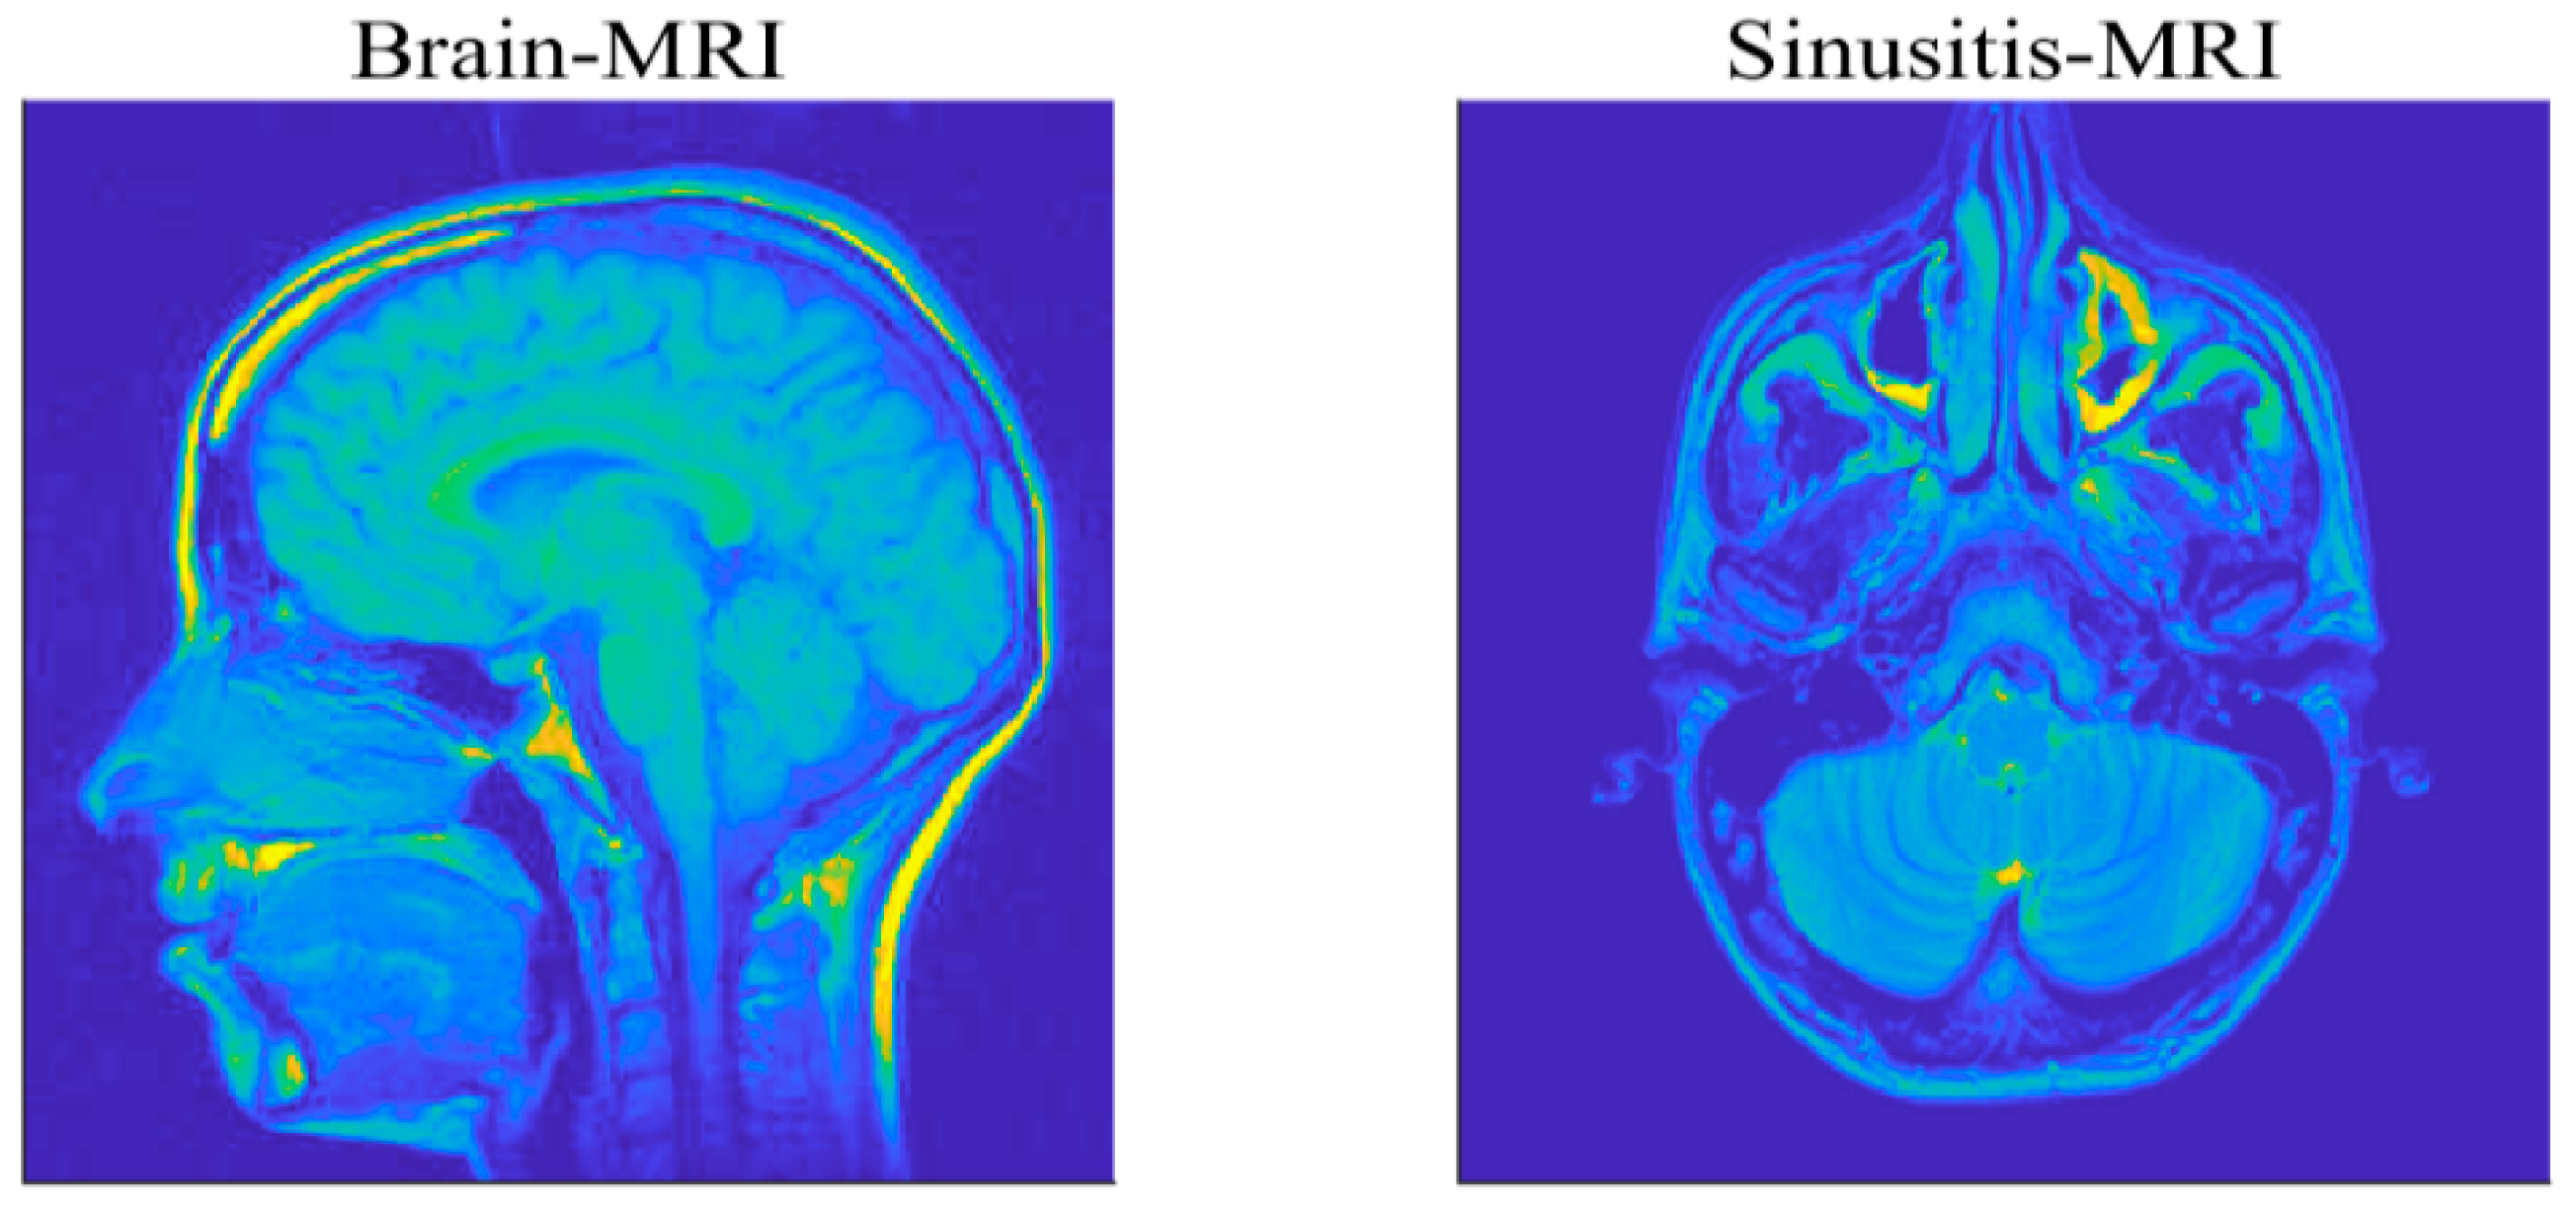

(2) Magnetic Resonance Imaging Example

To further verify the effectiveness and practicability of the proposed algorithms, this part will focus on the reconstruction of medical images. The used MRI images are of size 256 × 256 , for a brain MRI and sinusitis MRI, as shown in Figure 12, and evaluate the recovery performance by the value of PSNR. We utilize the Haar wavelets as the basis for sparse representation of the images. The compression ratio M/N is set as 0.4 and the measurement matrix is a partial DCT matrix. A Gaussian mixture model (GMM) ( f = ρ N ( 0 , σ 2 ) + ( 1 ρ ) N ( 0 , k σ 2 ) ) is taken to model the impulsive noise, where the parameters ρ ( 0 , 1 ) and k > 1 respectively control the proportion and the strength of outliers in the noise [19]. To ensure fairness of comparison, the λ in each algorithm is selected by providing the best performance in terms of relative error of recovery [22].

Figure 13 shows the recovered MRI images of all algorithms under the GMM noise with ρ = 0.9 , k = 1000 and SNR = 20 dB. The PSNR results are shown in Table 4. It can be seen that each algorithm can successfully reconstruct the two MRI images. Quantitatively, it is observed that the PSNR of the MRI images recovered using negentropy algorithms based on p norm have a higher value than those recovered by other compared algorithms and the negentropy algorithm based on 0.5 norm obtains the best recovery performance. Particularly, for the brain MRI image, the PSNR gains of negentropy + 0.5 over Huber-FISTA, YALL1 and LqLA-ADMM (q = 0.5) are 0.53 dB, 1.13 dB and 0.31 dB, respectively. Furthermore, Figure 14 presents the convergence curve of PSNR versus iterations in recovering the brain MRI image. It can be seen that compared with LqLA-ADMM (q = 0.5) and Huber-FISTA, the negentropy algorithm requires less iterations to converge. Thus, the proposed algorithm is more efficient for the recovery of MRI images in terms of accuracy and convergence speed.

Figure 12. Two test MRI images.

Figure 13. Recovery results of MRI images with the GMM noise: (a) brain MRI.; (b) sinusitis MRI.